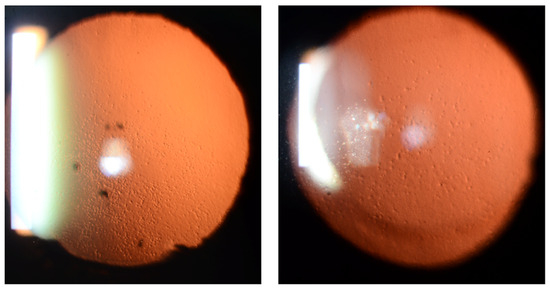

6. Analysis of Retroillumination Photography

- Gottsch, J.D.; Sundin, O.H.; Rencs, E.V.; Emmert, D.G.; Stark, W.J.; Cheng, C.J.; Schmidt, G.W. Analysis and documentation of progression of Fuchs corneal dystrophy with retroillumination photography. Cornea 2006, 25, 485–489. [Google Scholar] [CrossRef] [PubMed]

- Eghrari, A.O.; Garrett, B.S.; Mumtaz, A.A.; Edalati, A.E.; Meadows, D.N.; McGlumphy, E.J.; Iliff, B.W.; Gottsch, J.D. Retroillumination Photography Analysis Enhances Clinical Definition of Severe Fuchs Corneal Dystrophy. Cornea 2015, 34, 1623–1626. [Google Scholar] [CrossRef]

- Eghrari, A.O.; Mumtaz, A.A.; Garrett, B.; Rezaei, M.; Akhavan, M.S.; Riazuddin, S.A.; Gottsch, J.D. Automated Retroillumination Photography Analysis for Objective Assessment of Fuchs Corneal Dystrophy. Cornea 2017, 36, 44–47. [Google Scholar] [CrossRef]

- Soh, Y.Q.; Peh, G.S.L.; Naso, S.L.; Kocaba, V.; Mehta, J.S. Automated Clinical Assessment of Corneal Guttae in Fuchs Endothelial Corneal Dystrophy. Am. J. Ophthalmol. 2021, 221, 260–272. [Google Scholar] [CrossRef]